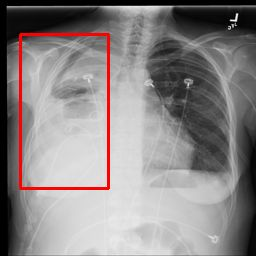

Deployments of artificial intelligence in medical diagnostics mandate not just accuracy and efficacy but also trust, emphasizing the need for explainability in machine decisions. The recent trend in automated medical image diagnostics leans towards the deployment of Transformer-based architectures, credited to their impressive capabilities. Since the self-attention feature of transformers contributes towards identifying crucial regions during the classification process, they enhance the trustability of the methods. However, the complex intricacies of these attention mechanisms may fall short of effectively pinpointing the regions of interest directly influencing AI decisions. Our research endeavors to innovate a unique attention block that underscores the correlation between 'regions' rather than 'pixels'. To address this challenge, we introduce an innovative system grounded in prototype learning, featuring an advanced self-attention mechanism that goes beyond conventional ad-hoc visual explanation techniques by offering comprehensible visual insights. A combined quantitative and qualitative methodological approach was used to demonstrate the effectiveness of the proposed method on the large-scale NIH chest X-ray dataset. Experimental results showed that our proposed method offers a promising direction for explainability, which can lead to the development of more trustable systems, which can facilitate easier and rapid adoption of such technology into routine clinics. The code is available at www.github.com/NUBagcilab/r2r_proto.